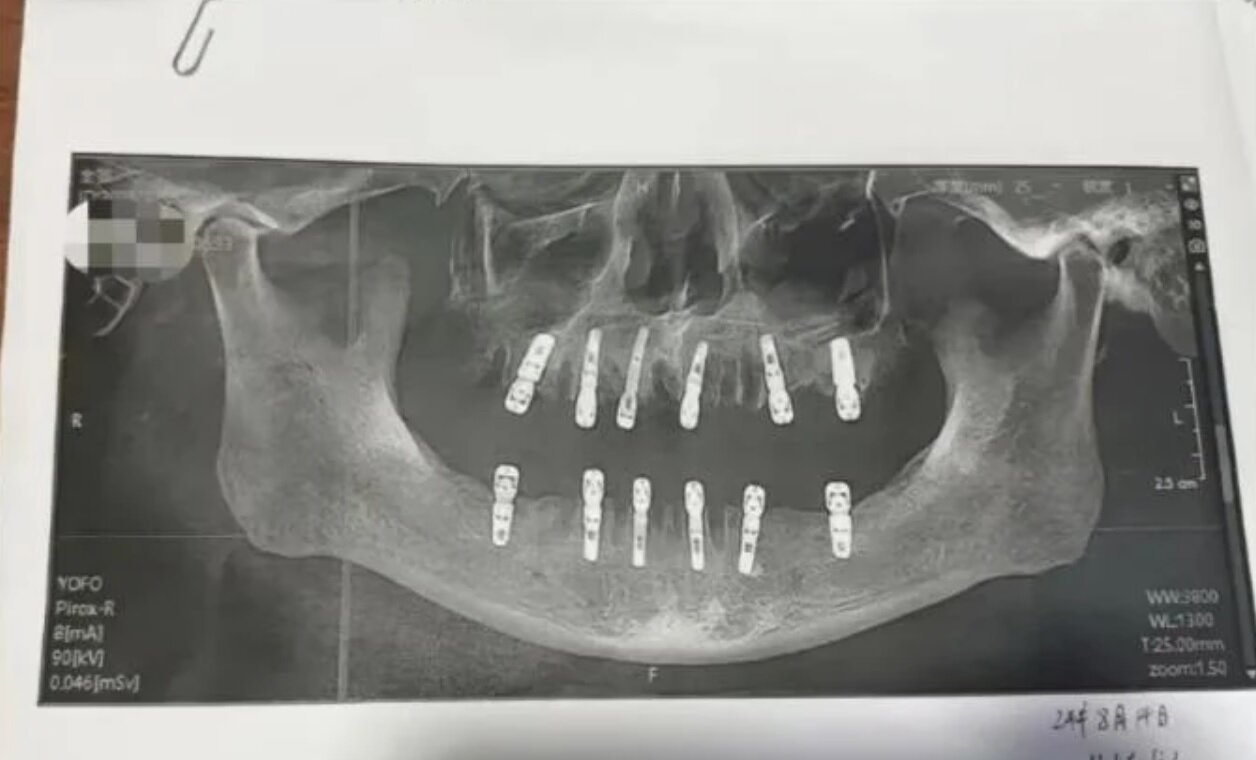

به گزارش خبرداغ به نقل از خبرآنلاین؛ نادیا زکالوند: خانم شو (shu)، ساکن شهر یونگکانگ از استان ژجیانگ چین، پس از مرگ پدرش در اثر سکته قلبی، از کلینیک دندانپزشکی محلشان شکایت کرد. این زن شواهدی مبنی بر اینکه در یک روز ۲۳ دندان پدرش کشیده و ۱۲ دندان برای او کاشته شده بود به دادگاه ارائه داد و مدعی بود که عوارض درمان دندانهای پدرش در این کلینیک، ۱۳ روز بعد موجب مرگ ناگهانی او شده است. خانم شو میگوید، پدرش تمام ۱۳ روز پیش از مرگش دردهای طاقتفرسا داشته است.

بنابر بررسیها، پدر خانم شو، با رضایت کتبی خود اجازه داد تا این درمان سنگین در یک روز انجام شود و یکی از دندانپزشکها که در درمان ریشه دندان، کشیدن دندان عقل نهفته و پروتز کامل تخصص کافی داشت تمام کارهای درمانی دندان پدر خانم شو را انجام داده بود.